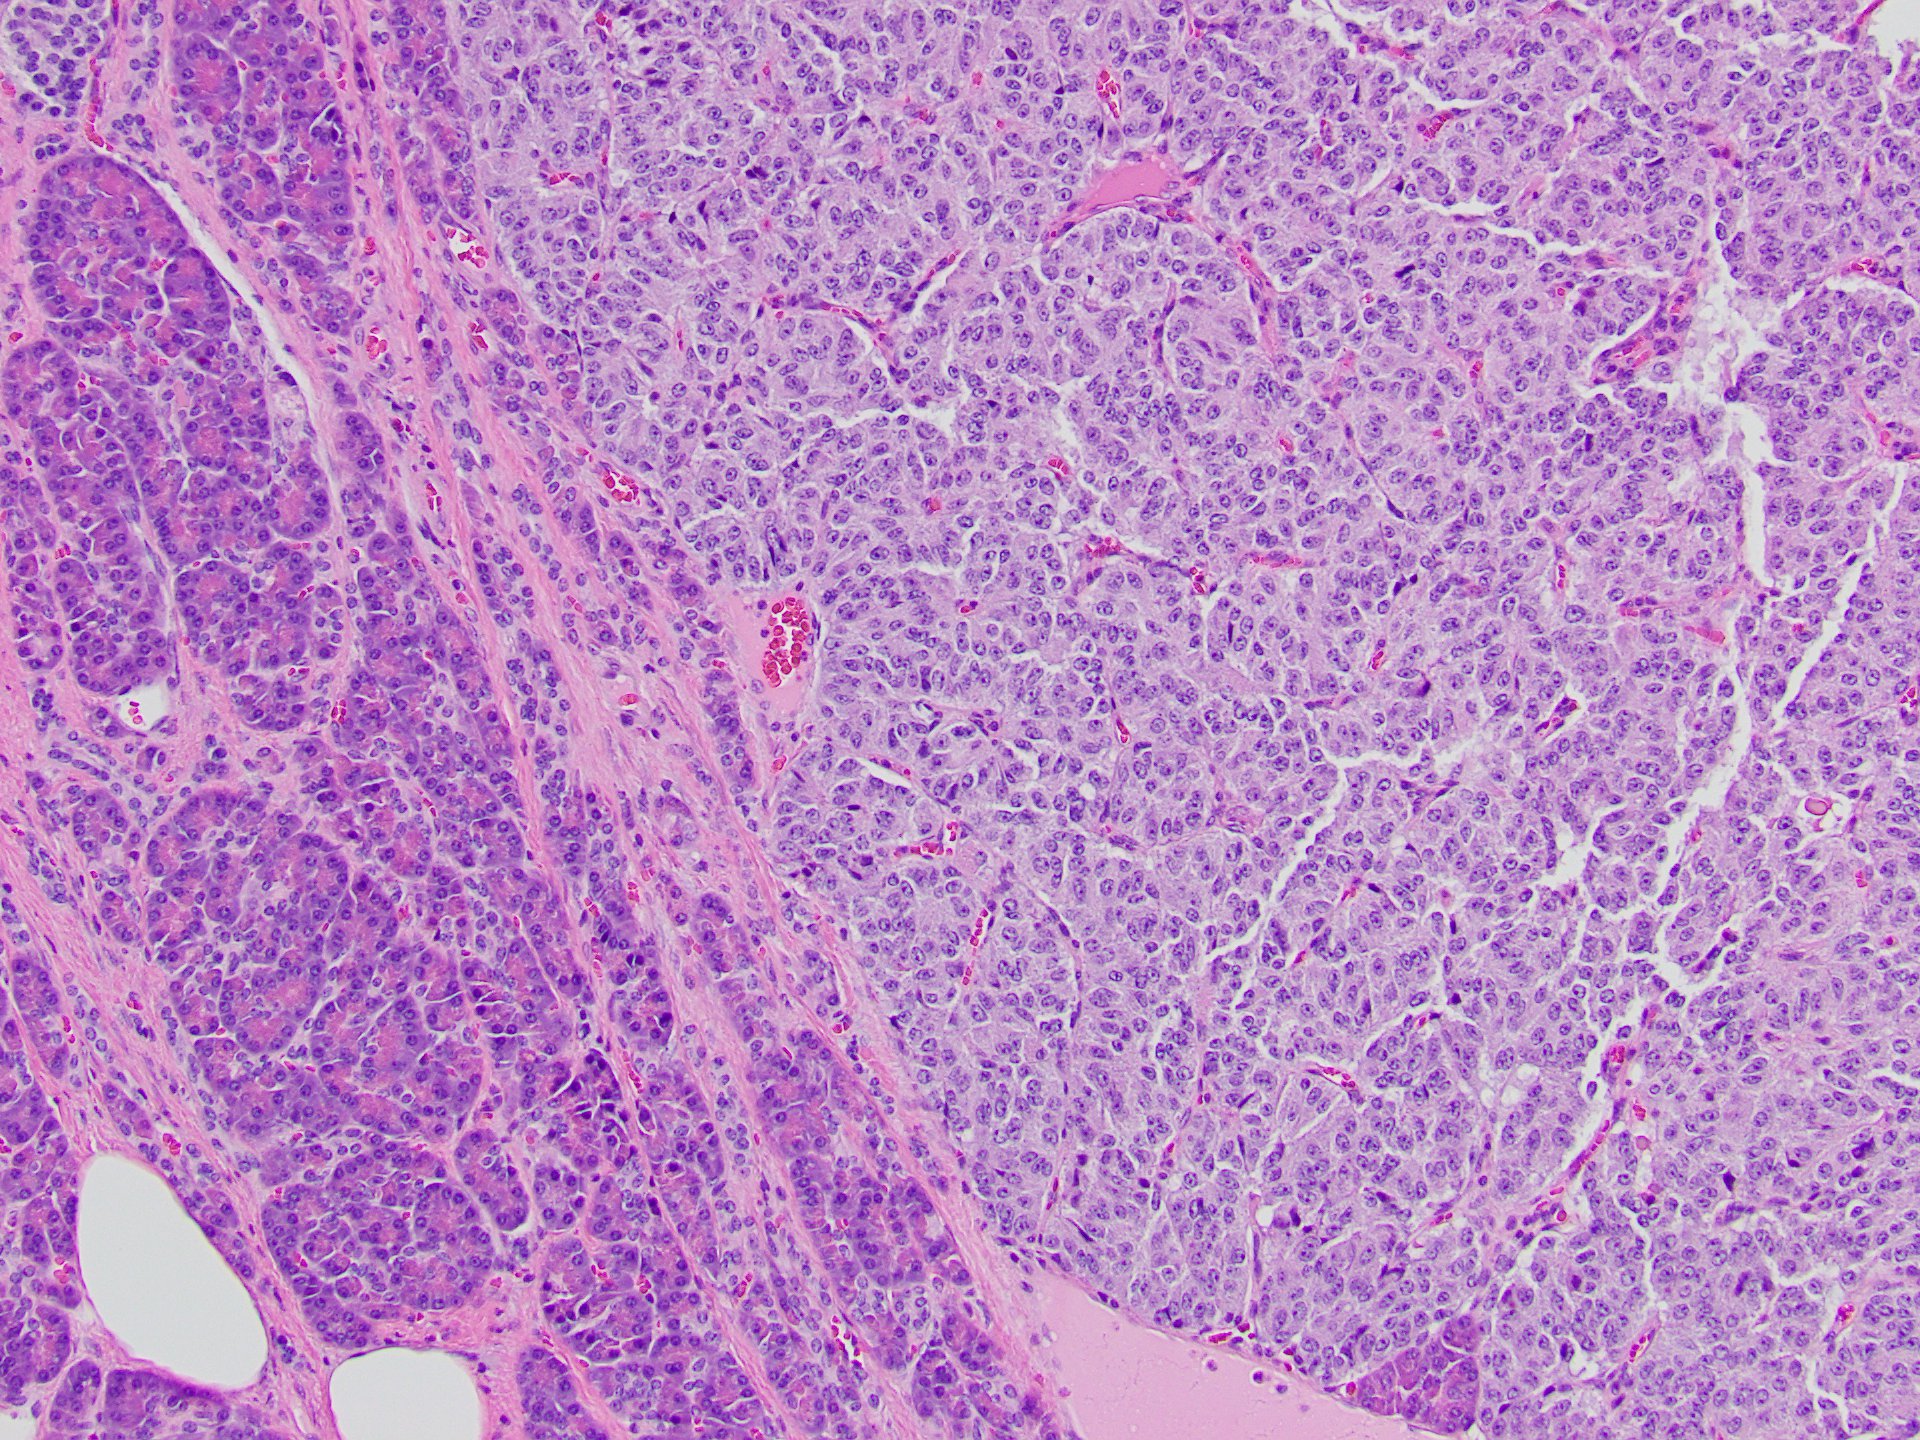

Abdominal CT showed a hypodense lesion in the tail of the pancreas. A follow-up MRI confirmed a 2.4 cm pancreatic mass and incidental bilateral non-obstructing renal calculi. Distal pancreatectomy was performed.

Gross examination of the distal pancreatectomy and splenectomy specimen revealed a 2.6 cm firm, well-circumscribed, homogeneous, yellow/tan intrapancreatic tumor and an unremarkable spleen.

On microscopy, the tumor consisted of a monotonous population of round cells with dispersed fine chromatin, prominent central nucleoli, and a moderate amount of cytoplasm (Figures 1-5). Also, multiple small neuroendocrine lesions of similar appearance (microadenomas; Figures 6-9) were seen.